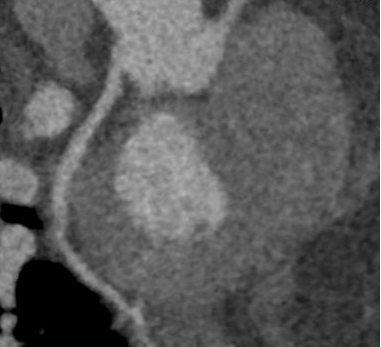

回旋支近端软斑块并管腔轻度狭窄

RCA右冠状动脉多发软斑块并管腔轻度狭窄

冠状动脉CTA检查精准找出胸痛元凶

临床医师结合影像结果,迅速明确诊断,

给予对症改善心脏循环治疗,

4天后张先生好转出院。